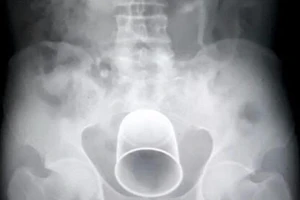

Phẫu thuật cấp cứu lấy chai nhựa dài 20cm trong hậu môn người đàn ông